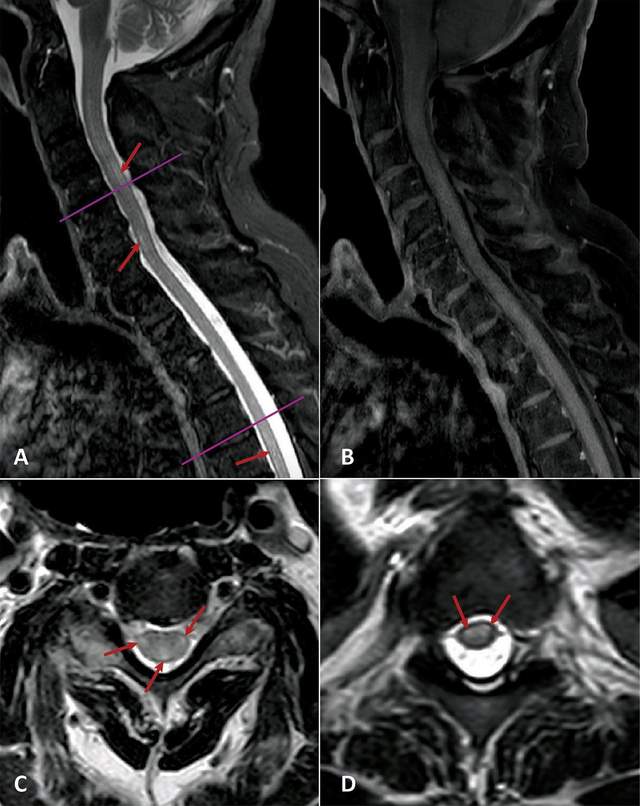

Вчені встановили, що коронавірус може стати причиною надзвичайно рідкісного неврологічного захворювання, яке супроводжується запаленням сірої і білої речовин у спинному мозку.

Гострий поперечний мієліт – це запалення спинного мозку, яке може викликати біль, параліч і проблеми з чутливістю. Захворювання дійсно рідкісне: 1,34-4,6 випадку на мільйон людей на рік. Під час пандемії COVID-19 лікарі фіксують збільшення кількості випадків захворювання.

У всіх пацієнтів, розглянутих у дослідженні, був параліч і втрата чутливості, а медична візуалізація показувала наявність уражень спинного мозку.